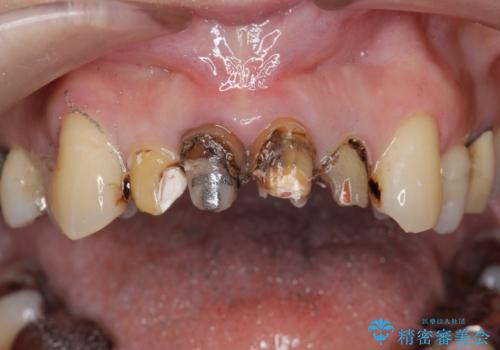

- クラウン周りの黒ずみが気になり、審美性の改善を求めて来院されました。

以前に治療した前歯クラウンは月日が経過することで劣化・歯肉の位置変化を引き起こし審美障害を引き起こしています。

劣化したクラウンを除去し、再発した虫歯を徹底的に除去したのち根管治療・ファイバーコア築盛を行いジルコニアクラウン製作へと移ります。